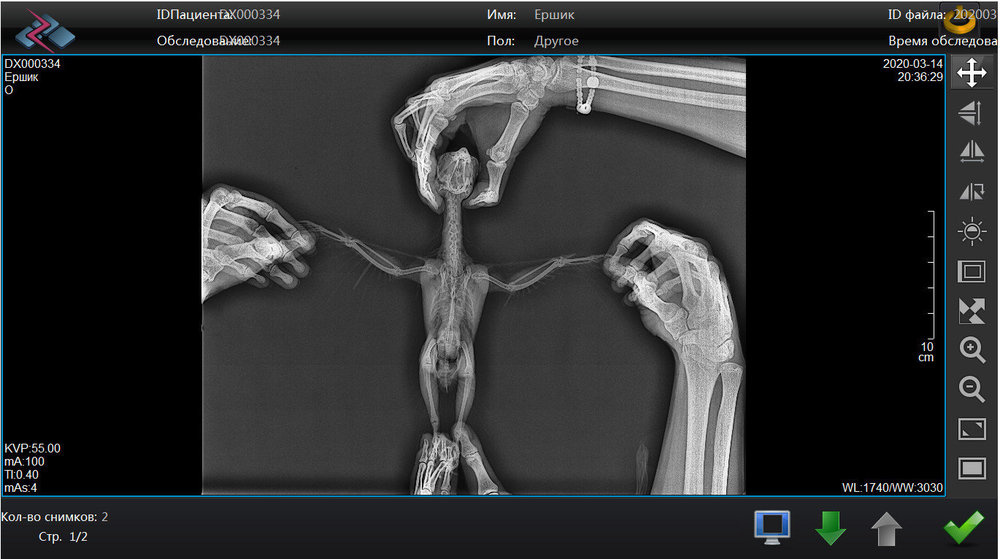

Pipka Опубликовано 25 марта, 2020 Автор #56 Опубликовано 25 марта, 2020 19.03.2020 в 19:28, Город сказал: Держитесь!! @Город , пасип! Мы держимся. 19.03.2020 в 20:21, Наташенька2 сказал: Держу за вас кулачки, все будет хорошо у вас!?? @Наташенька2 , спасипки! 20.03.2020 в 07:59, Marina-P сказал: @Pipka держитесь! Вы молодчина! @Marina-P , Спасибо! 20.03.2020 в 08:32, амазон сказал: Лучше до победного. @амазон , спасибки, я тоже так думаю. 22.03.2020 в 09:06, Лефф сказал: У моего цирковирус. Пневмония была тяжелая, правда не выясняли этиологию. Очень хорошо и быстро помогли ингаляции по 30 мин каждый вечер масла чайного дерева (аромалампа под накидкой на клетку). Противогрибковыми свойствами обладает масло орегано. Это не совет, это, возможно, повод поискать в этих направлениях. @Лефф , спасибо за помощь. Мы купили розмарин и орегано. чайного дерева я не нашла. Аромалампу я что-то боюсь. просто капала ему в обычную ингаляцию и в распылитель. мне кажется, что после ингаляций намного лучше дышит нос. Всем огромное спасибо за помощь и поддержку. У нас большой прогресс. Ёршик перестал хрипеть и хлюпать носом. Нос почти зажил, но все равно жутко чихает. И еще продолжаются движения головой с открытым ртом будто тошнит. Многие мне пишут, что так проявляет себя аспергиллез. Анализ на посев из зоба ждем со дня на день. Парень повеселел, уже не хохлится и не ершится как раньше. Я сняла видео - выложу ниже. Посмотрите если не сложно на его апчихи и на эти движения головой. Кто-то из вас скажет - мол, ничего страшного в этом нет, все попугаи так делают - типо горло прочищают. Да, я знаю, но он так делает почти постоянно. Очень очень часто. Словно бедняжке что-то мешает там. Если у кого такое было во время болезни - напишите плиз. Будем вам признательны. Еще хочу выложить здесь наши рентгены с пневмонией и результаты посевов на антибиотики и пробиотики с макрофагами. Может кому-то будет на пользу. Тоже буду благодарна если глянете - может кто разбирается. Подскажите плиз.

Pipka Опубликовано 18 апреля, 2020 Автор #73 Опубликовано 18 апреля, 2020 11.04.2020 в 21:10, Мария_К сказал: @Pipkaв надежде на хорошие новости от вас. @Мария_К , И ура!!!! Они таки хорошие!!!!!!! Люди, народ, поздравьте нас с Ёршиком!!!!!!! Мы поправились!!!! Не надо больше уколов, мерзких гадких заворачиваний в полотенце и принудительных выпаиваний горьким лекарством. МЫ ЗДОРОВЕНЬКИЕ!!!!! Посмотрите какой у нас чистенький и светленький рентгенччииккккк!!!!!!! Никаких затемнений, никаких гранулем или остаточных швов на легких. В сравнении с тем что было - день и ночь. Даже мне стало понятно и видно все. Мы поправились. По клинической картине: чихов нет, хрипов-сипов нет, нос чистейший, морду не трет, головой не дергает. Чуть позже выложу ввидео с ним. Пока вот рентген. Господи, как же я счастлива!!!!! Про липому все также. Без изменений. Но нам сказали что это фигня. Если будет правильно питаться и двигаться то больше чем есть не вырастет...

Pipka Опубликовано 18 апреля, 2020 Автор #74 Опубликовано 18 апреля, 2020 Извините, полосы - это мерцание на компе от телефона. Мне так не терпелось, что я прямо с компа на телефон щелкнула. а так ответ на диске, а у меня дома дисковода нема.